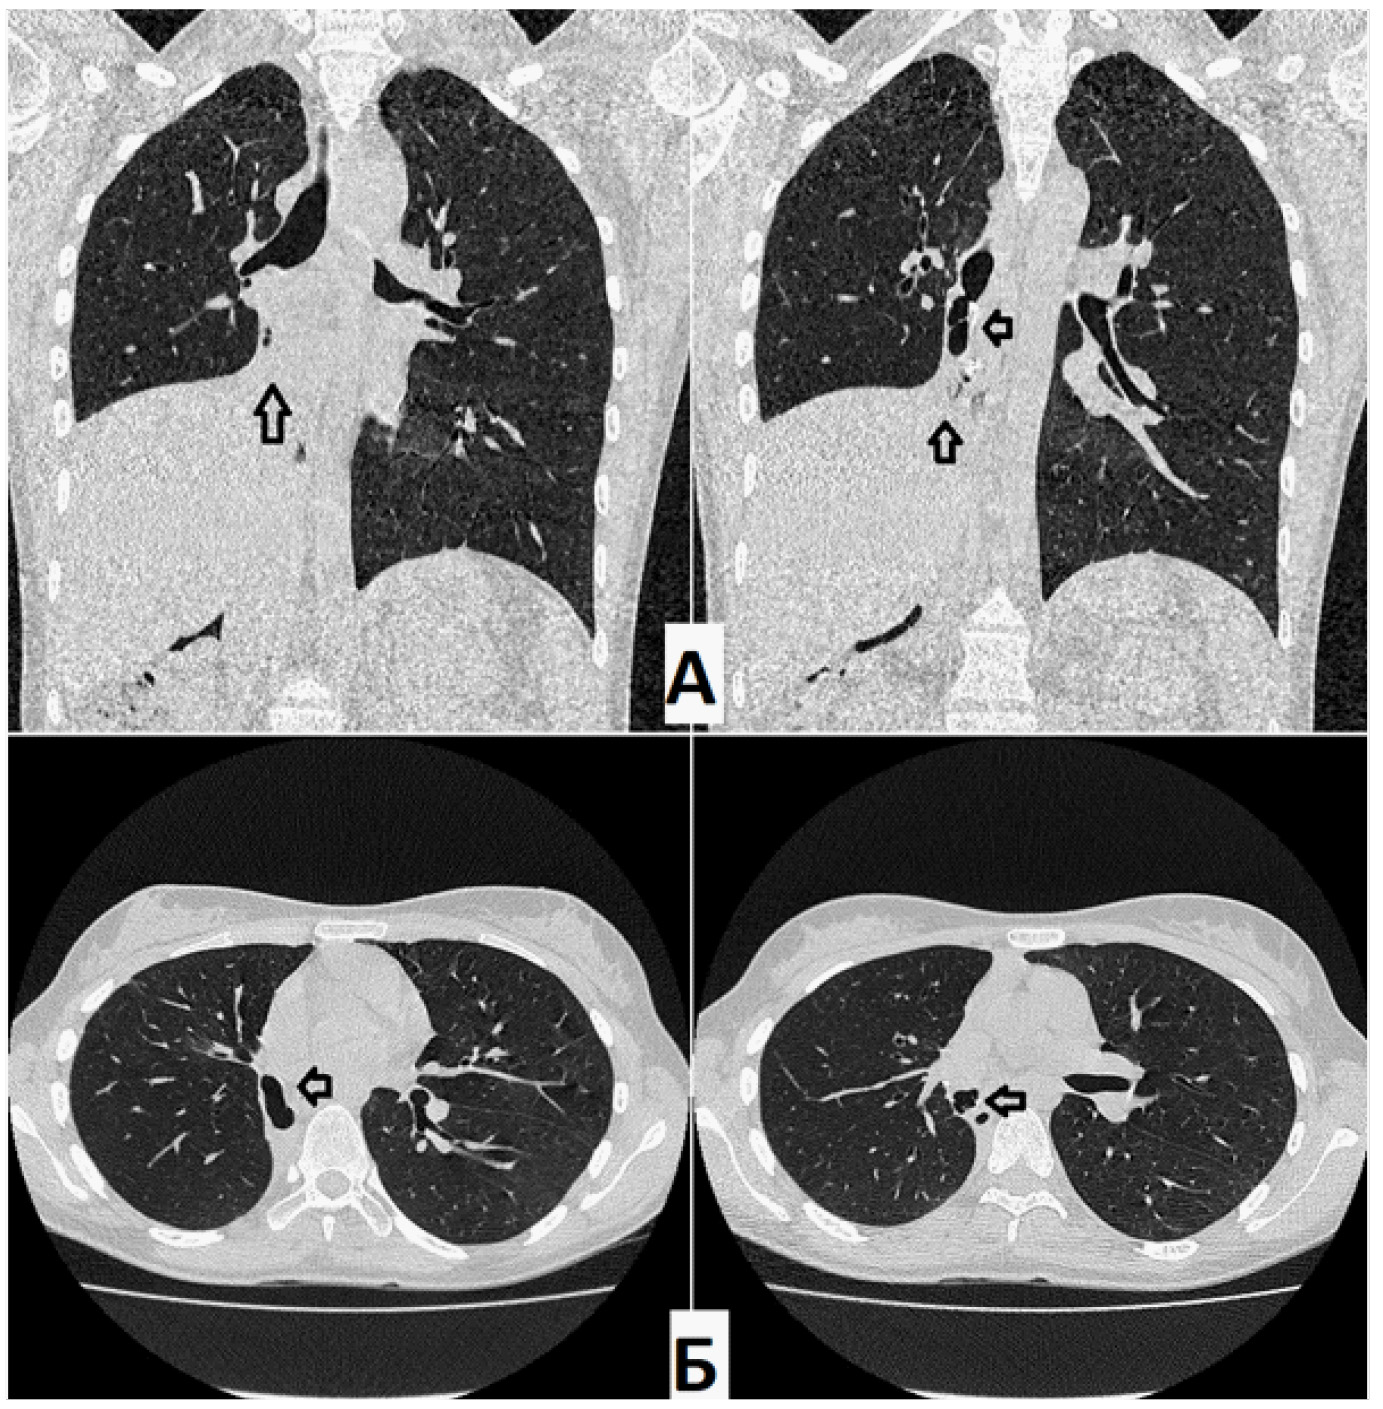

Через 1,5 месяца после операции пациентке выполнено КТ ОГК (07.09.2021.) (рис. 4): определяются косвенные признаки бронхоплеврального сообщения между культей правого промежуточного бронха и плевральной полостью, полость соприкасается с линией резекции культи (цепочки скоб). В динамике – увеличение объема ОПП в нижних отделах справа, как латерально, так и парамедиастинально. В оставшихся отделах правого легкого без свежих патологических изменений. Тень средостения располагается срединно, правый купол диафрагмы приподнят до уровня VI межреберья.

Рис. 4. Компьютерная томография (А – фронтальная проекция; Б – аксиальная проекция) через 1,5 месяца. Остаточная плевральная полость справа латерально и парамедиастинально. В динамике – полость увеличилась в размерах